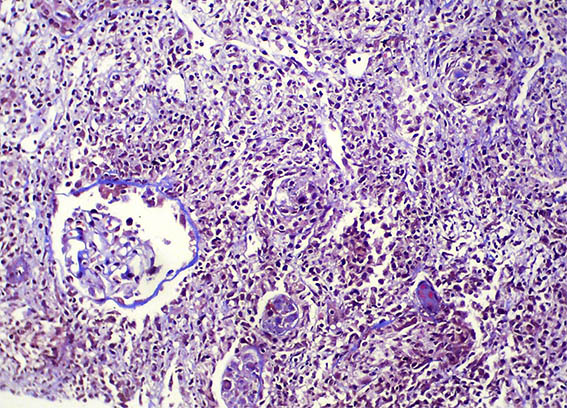

The patient is a 32-year-old man, kidney transplanted 18 months ago due to end-stage renal disease of unknown cause. A cellular rejection episode was evidenced in the first year. Good kidney function in the last control (16 post-transplantation months). Now in a new control the serum creatinine has risen to 1.9 mg/dL. Mild proteinuria and microscopic hematuria, no other abnormalities.

See the images of the renal allograft biopsy.

Figure 2. H&E, X200.